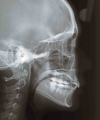

| 治療前後の比較

|